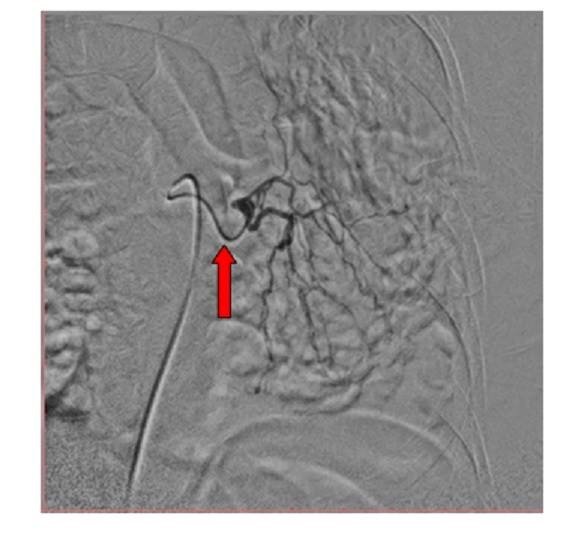

Common bronchial-intercostal trunk. Both the right bronchial artery and superior intercostal artery arise from a common trunk. The bronchial artery (straight red arrow) follows the course of the mainstem bronchus, whereas the intercostal artery follows the undersurface of the rib (curved arrow). Abnormal vessels & blush (Straight white arrow).